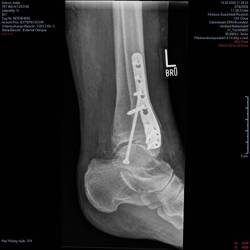

Vor zwei Jahren hatte ich mir bei einem Sturz in Folge einer Ohnmacht die linke Hand. Dieses Mal bin ich auf Glatteis ausgerutscht, gestürzt und habe mir eine Sprunggelenksluxations-

fraktur amRead more